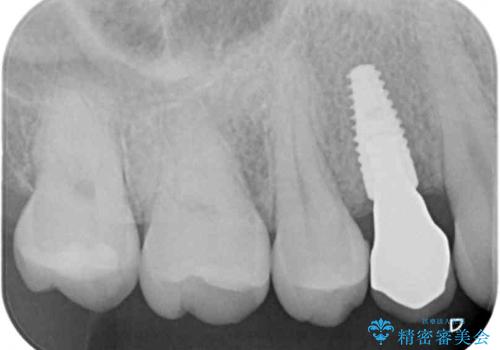

ジルコニアカスタムアバットメントは、歯肉ラインに金属が見えにくいというだけでなく、クラウンを装着する土台の形が天然歯と近い形態となるため、清掃性が高く歯肉が腫れにくいというメリットがあります。

インプラントは、人工骨を用いた際の骨誘導能が比較的高いとさせるストローマン社のSLActiveを使用しました。